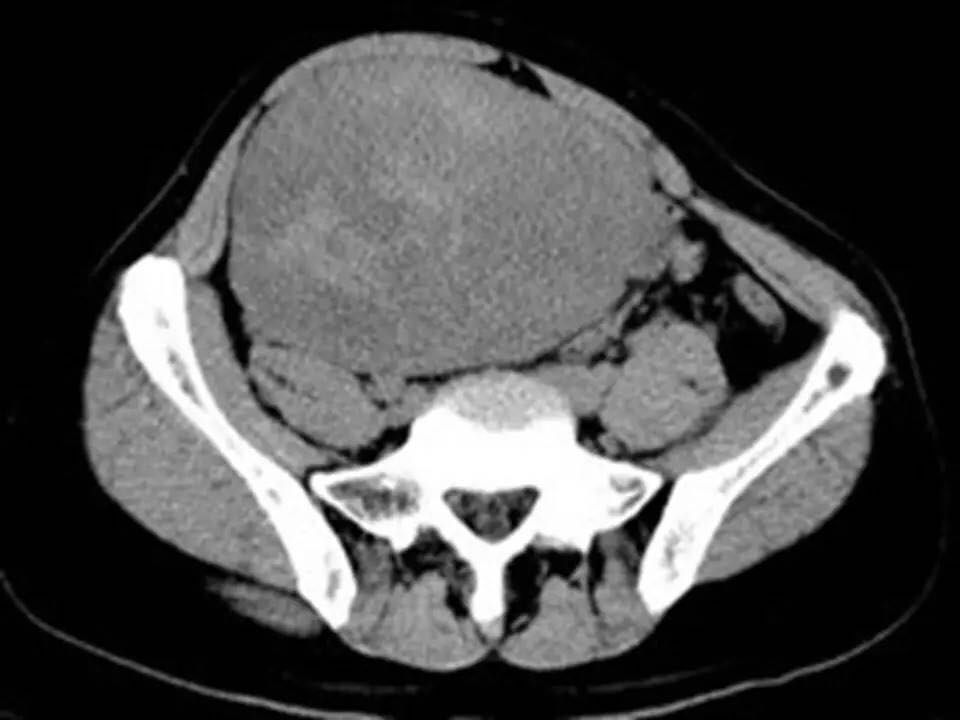

MRI表现,腹盆腔见不均质肿块,与肌肉相比为等低密度,强化不明显。T1WI信号均匀,T2WI高低混杂信号,增强后渐进性强化,病变各序列可见斑片状低信号区。 诊断,腹腔侵袭性纤维瘤病。

AF的影像学表现具有一定特征性。影像上表现为边界欠清的软组织肿块,钙化、出血少见,即便在较大的肿瘤中也看不到中央性坏死。病灶CT密度欠均匀,与邻近骨骼肌相近,强化不明显。T1WI信号基本均匀,明显或中度强化,典型强化方式呈渐进性。所有序列中都可以看到一定的低信号区,在病理上相对应的为病变内胶原纤维丰富的区域,此区域强化较轻。 侵袭性纤维瘤病虽然少见,但是平常工作中需要考虑到侵袭性纤维瘤病的诊断,尤其是中年女性腹腔的肿块。MRI为最佳的检查方法,可以显示一定的影像学特征。